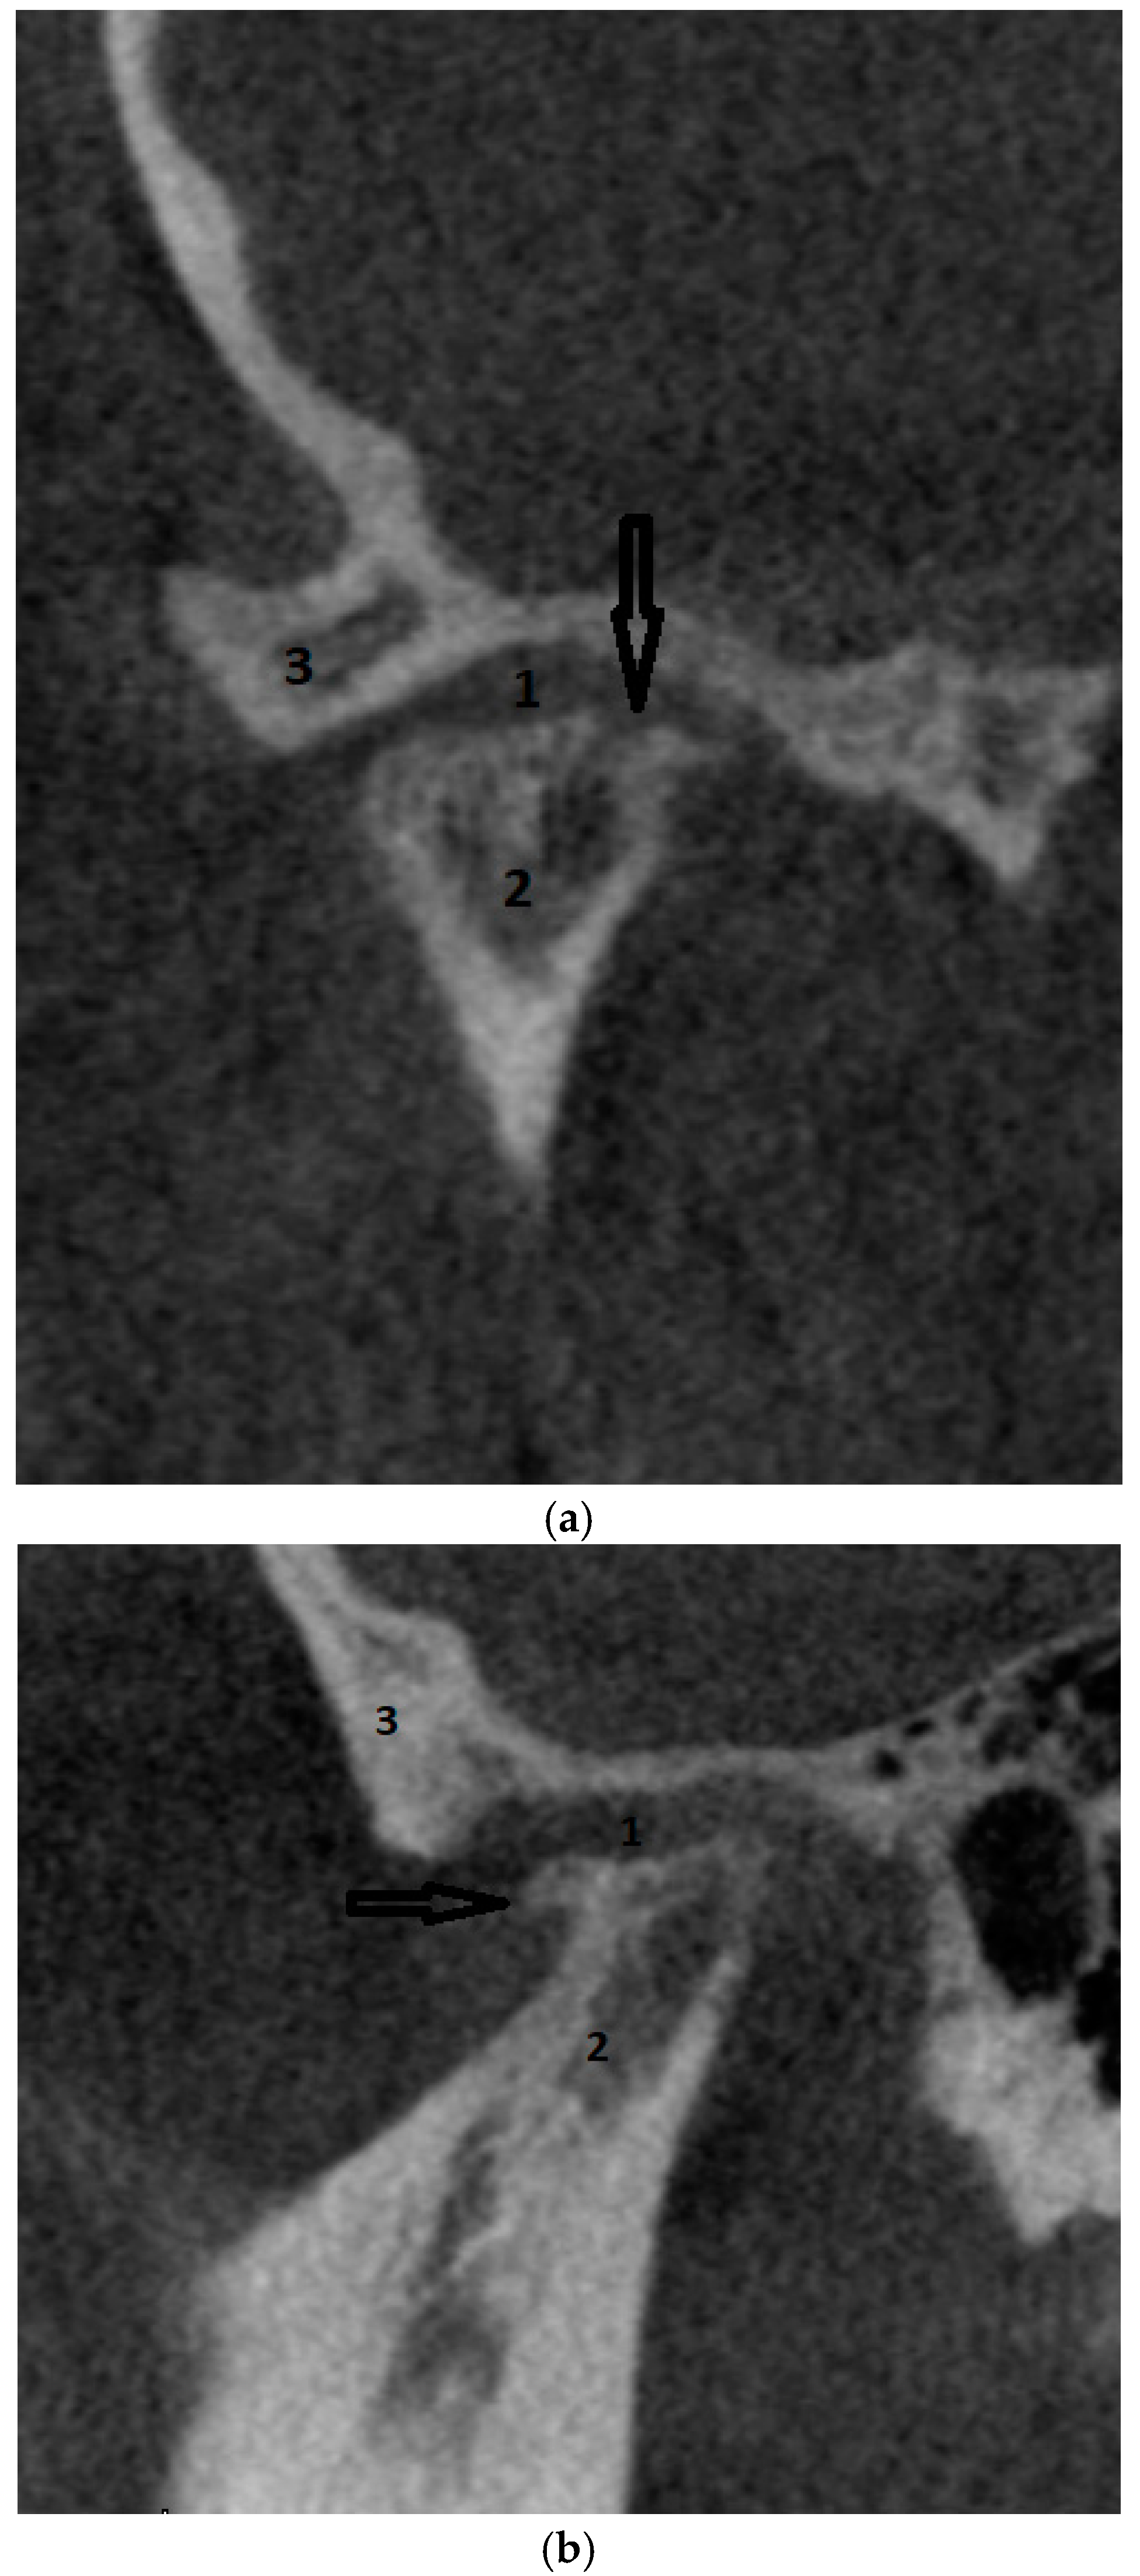

- Dhabale, G.S.; Bhowate, R.R. Cone-Beam Computed Tomography for Temporomandibular Joint Imaging. Cureus 2022, 14, 31515. [Google Scholar] [CrossRef]

- Almashraqi, A.A.; Sayed, B.A.; Mokli, L.K.; Jaafari, S.A.; Halboub, E.; Parveen, S.; Al-Ak’hali, M.S.; Alhammadi, M.S. Recommendations for standard criteria for the positional and morphological evaluation of temporomandibular joint osseous structures using cone-beam CT: A systematic review. Eur. Radiol. 2024, 34, 3126–3140. [Google Scholar] [CrossRef] [PubMed]